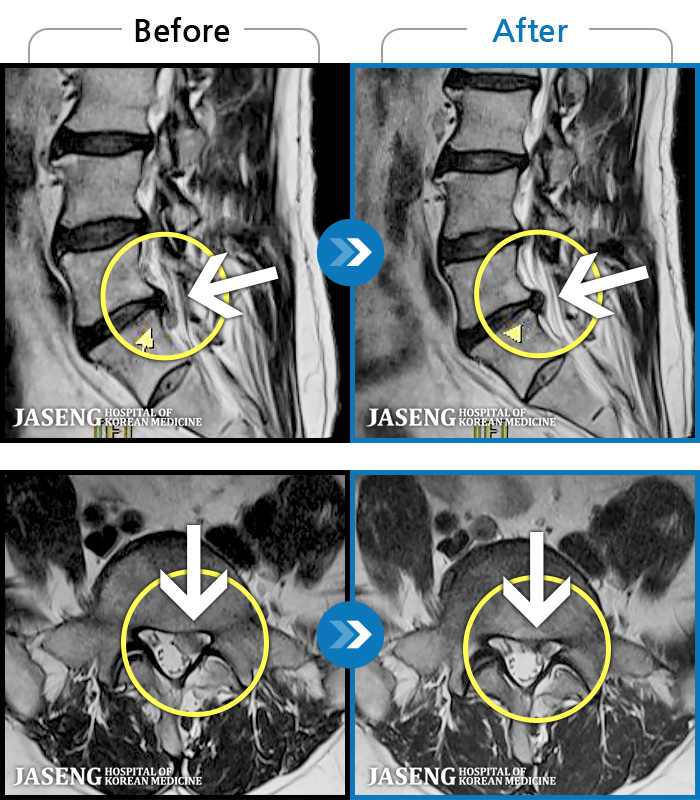

허리디스크

광주 · 김동은 원장

양측 허리부터 양측 골반까지 당기는 통증, 양측 하지 후면으로 이어지는 통증

촬영시기

2022.09.05 ~ 2024.05.06

2024.05.24